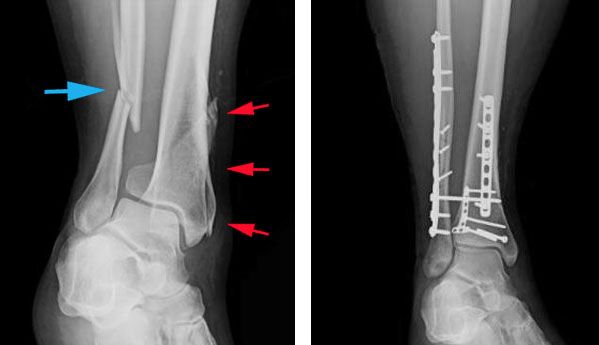

(A) A 32-year-old female with simple fracture of the ...

(A) A 32-year-old female with simple fracture of the ... from www.researchgate.net